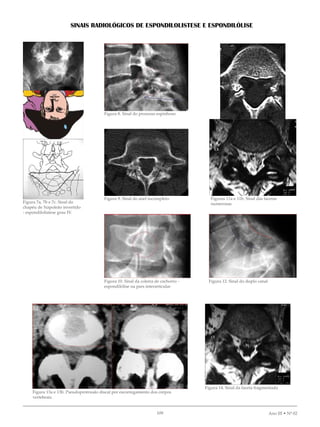

SINAIS RADIOLÓGICOS DE ESPONDILOLISTESE E ESPONDILÓLISE

Figura 7a, 7b e 7c. Sinal do

chapéu de Napoleão invertido

- espondilolistese grau IV.

Figura 8. Sinal do processo espinhoso

Figura 9. Sinal do anel incompleto

Figura 10. Sinal da coleira de cachorro -

espondilólise na pars interarticular

Figuras 11a e 11b. Sinal das facetas

numerosas

Figura 12. Sinal do duplo canal

Figura 13a e 13b. Pseudoprotrusão discal por escorregamento dos corpos

vertebrais.

Figura 14. Sinal da faceta fragmentada